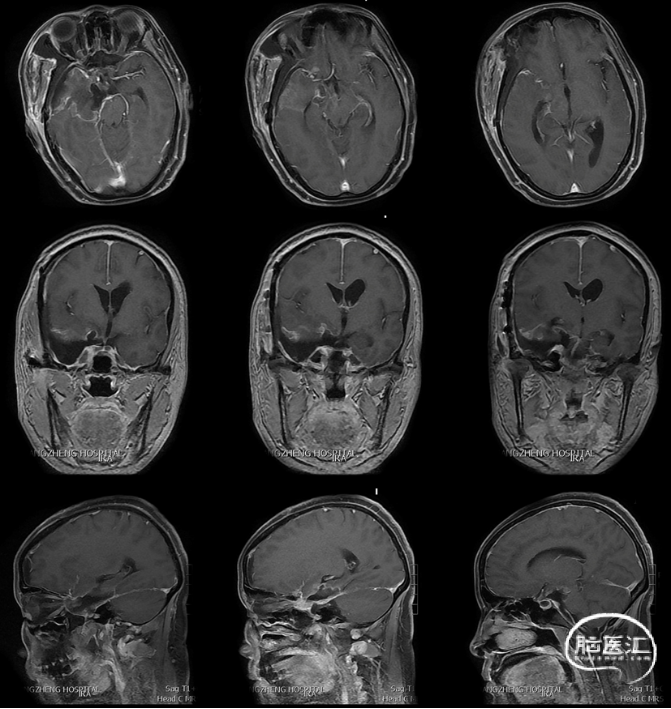

MRI、CT、CTA及三维重建显示右侧鞍旁见不规则信号影,病灶跨颅中、后窝,直径约4.5cm,推挤并包绕右侧颈内动脉及分支、大脑后动脉和基底动脉及分支,MRI显示T1呈等信号影,T2呈高信号影,FLAIR呈高信号,脑实质可见瘤周水肿,增强后均匀强化,脑干受压明显。

诊断:右侧大型蝶岩斜区脑膜瘤。